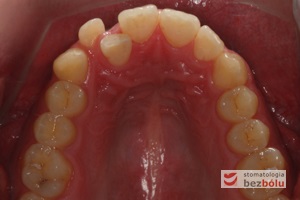

Młody 28-letni, pogodny, stale uśmiechnięty pacjent zgłosił się celem korekcji wad zębowych ograniczających pełną ekspresję uśmiechu. Głównym problemem był dodatkowy siekacz boczny (dwójka) po stronie prawej w łuku górnym. Dodatkowy ząb spowodował stłoczenia pozostałych zębów w łuku górnym oraz przesunięcie linii pośrodkowej. Obliczenia dostępnego miejsca dla siekacza bocznego wpłynęły na wybór zęba przeznaczonego do ekstrakcji. Usunięto dwójkę ustawioną dowargowo, zaś jej „siostrę bliźniaczkę” skierowaną w stronę podniebienia wprowadzono do łuku zębowego w drodze leczenia ortodontycznego. Problemem było szczelne zamknięcie szpary poekstrakcyjnej z powodu nadmiaru miejsca w kości. Wyrównano linię pośrodkową. Leczenie przeprowadzono jednym łukiem ortodontycznym górnym, dolny łuk zębowy nie wymagał założenia aparatu. Po zdjęciu zamków korekcję detali przeprowadzono z użyciem pozycjonera wykonanego w technice termoformingu. Stabilizację efektów leczenia zapewnił stały retainer klejony do powierzchni podniebiennych siekaczy górnych.